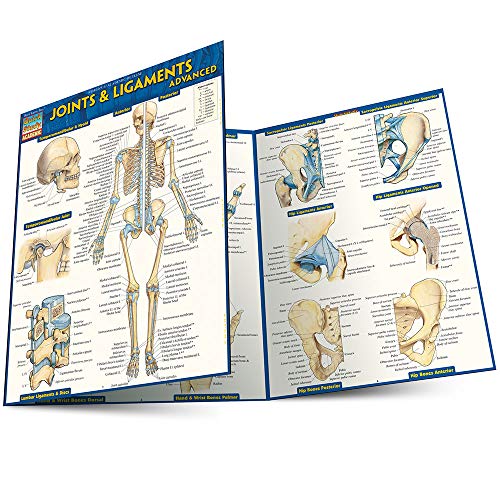

Joints & Ligaments Advanced QuickStudy Laminated Reference Guide (Quick Study Academic)